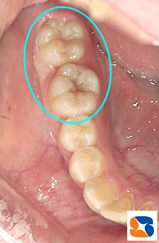

小学生 奥歯の茶色の溝

コラム「小学生 奥歯の茶色の溝」の画像